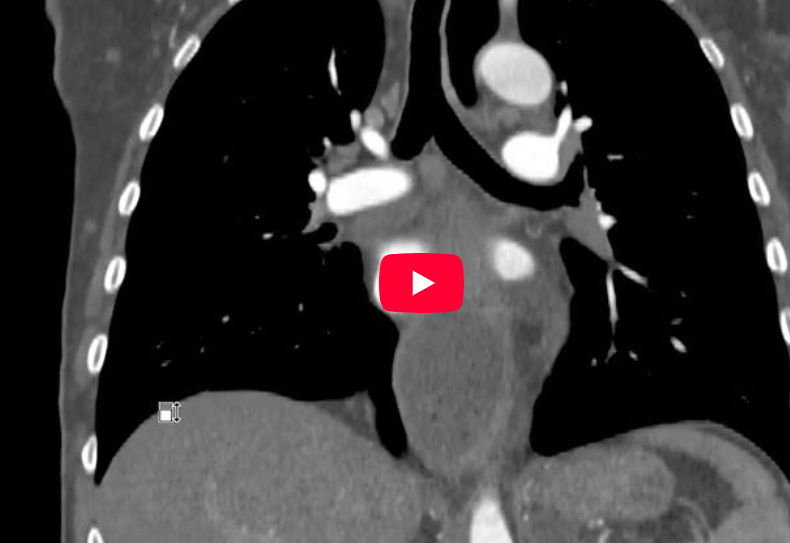

CAZ nr 110: Tumoră de joncţiune eso-gastrică

Video 1: reconstrucție axială torace după achiziție în timp arterial cu sincronizare ECG pentru arterele coronare

Video 2: reconstrucție sagitală torace după achiziție în timp arterial cu sincronizare ECG pentru arterele coronare

Video 3: reconstrucție coronală torace după achiziție în timp arterial cu sincronizare ECG pentru arterele coronare

Discuţie caz nr 110: pacientul a efectuat examinare cardioCT cu sincronizare ECG pentru dureri toracice cu caracter anginos. Se remarcă creștere de volum a esofagului toracic pe toată lungimea ce are conținut în principal lichidian cu nivel hidro-aeric ce se decalibreaza la nivelul joncţiunii eso-gastrice unde se pune în evidență îngroșare parietală circumferențială cu aspect tumoral.

DE LUAT ACASĂ!!! La examinarea CT esofagul normal are formă ovoidală, cu un diametru luminal transversal mai mare decât cel antero-posterior, de obicei nedepășind 10 mm. Prezența lichidului, a nivelului de lichid aerian sau a lumenului umplut cu aer care depășește 10 mm în diametru transversal este anormală și indică obstrucție sau tulburare de motilitate. Imagistica CT este deosebit de importantă in evaluarea esofagului pentru pacienții cu contraindicații pentru gastroscopie, care este metoda principală utilizată pentru evaluarea bolilor esofagiene. CT este indicat de primă intenție pentru stadializarea TNM, util mai ales pentru stadiile avansate (majoritatea pacienților), situație în care poate exclude tratamentul chirurgical și permite planificarea tratamentului neoadjuvant sau paliativ